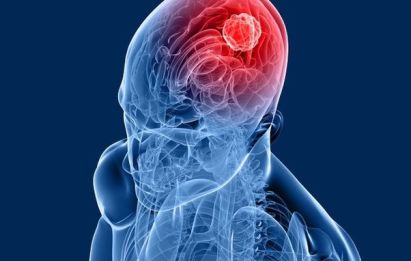

Benign Brain Tumor

A tumor is a mass of tissue that’s formed by an accumulation of abnormal cells. Normally, the cells in your body age, die, and replaced by new cells. With cancer and other tumors, something disrupts this cycle. Tumor cells grow, even though the body does not need them, and unlike normal old cells, they don’t die. As this process goes on, the tumor continues to grow as more and more cells are added to the mass.

Benign brain tumor usually have a distinct tumor border, and rarely spread or invade surrounding brain tissue. Though the word ‘benign’ may sound harmless, a benign tumor located in a vital area of the brain can be life threatening or fatal without treatment. No one knows what causes brain tumor; there are only a few known risk factors that have been established by research.

The benign brain tumor are determined using MRI and CT scans. This tumor usually grows slowly, but it does not attack the tissue area or spread to other organs. The most common brain tumor can be removed and usually, it will not repeat after removal. The exact cause of benign tumor can not be identified, but researchers have suggested that risk factors may come from family history, exposure to radiation and chemistry.